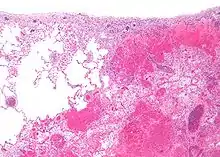

| Micrograph of a pulmonary infarct (right of image) beside relatively normal lung (left of image). H&E stain. | |